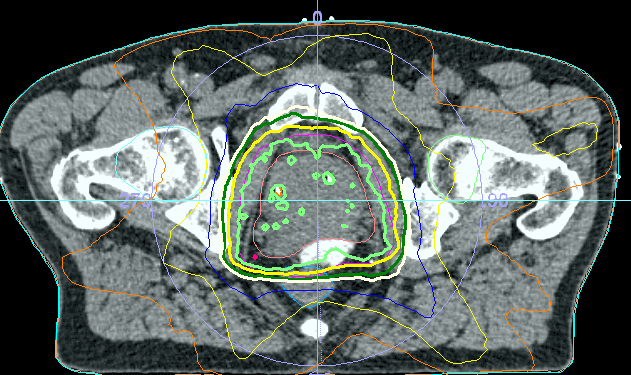

Consultation on radiation for prostate cancer including brachytherapy (seed implantation or HDR); modern organ-preserving therapy with gold markers and spacers